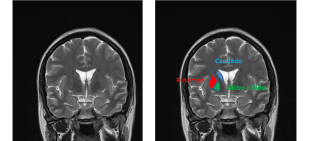

1. Calcificaciones bilaterales localizadas en el estriado (caudado-putamen), globo pálido y núcleo dentado (ver la figura 1. para localización de estas estructuras) visualizado en imágenes de TAC cerebral.

Las calcificaciones cerebrales fisiológicas que aparecen con la edad son pequeñas, de aspecto punteado aunque pueden confluir y limitadas al globo pálido (ver entrada). La calcificaciones que se observan en la calcinosis idiopática estriado-pálido-dentada son más extensas, afectan además del globo pálido al putamen y al nucleo dentado y son confluentes (ver esta imágenes en esta página).